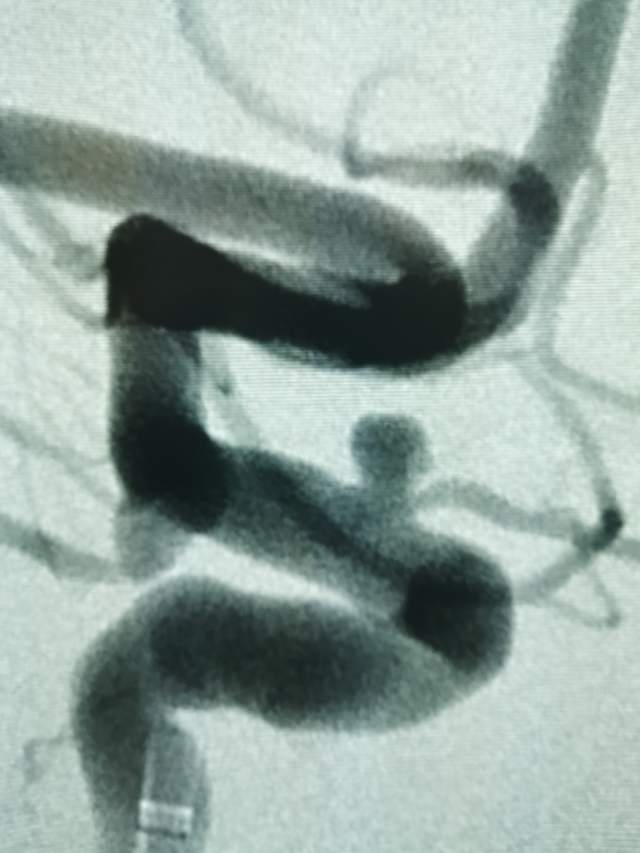

44岁盐城帅哥,因“头痛3天”发现静脉窦血栓合并“颅内动脉瘤“来诊。颅内动脉瘤之一是瘤体累及眼动脉的相对宽颈微小动脉瘤(2.5mm),此部位动脉瘤存在破裂出血的风险,而且静脉窦血栓的治疗也会加重此风险,有必要同步先消除这个潜在的风险。病变累及眼动脉,如果治疗过程中受到累及存在失明风险,需要重点保护。最终,采用一个支架一个圈的“简约模式:花费少,效果好”结束手术,眼动脉保留良好。